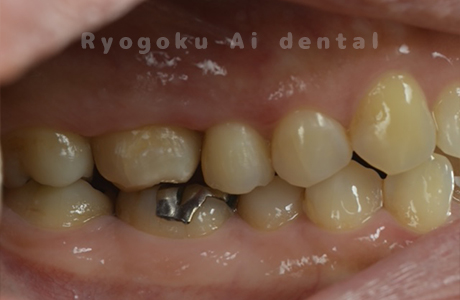

Case17

- 重度カリエス

- 治療内容

- クラウンレングスニング、ジルコニアクラウン修復

- 治療費用

- 209,000円

被せ物がよく外れるとのことでご来院された患者様です。クラウンレングスニングを行い、被せ物の治療を行いました。